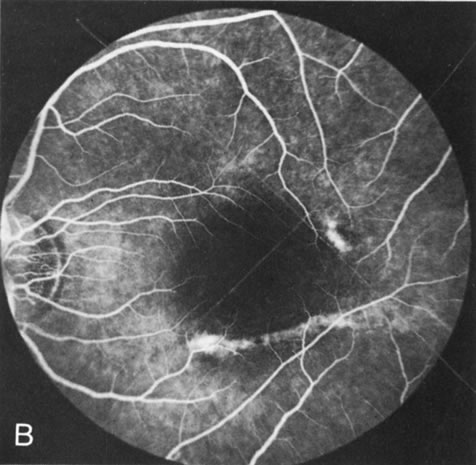

Fig. 1. Retinitis pigmentosa. A. A typical area of bone spicule pigmentation. B. Diffuse dye leakage is apparent throughout the posterior pole. C. The early angiogram shows dilated and irregular retinal radial peripapillary capillaries and perifoveal retinal capillaries. D. Leakage from these vessels are evident in the late angiogram.

Dye leakage in RP may occur from the retinal vessels or at the level of the retinal pigment epithelium (Fig. 1B).2–4 The leakage may be seen in the macula and posterior pole, along the vascular arcades in the distribution of the radial peripapillary capillaries, and in the periphery (where an exudative vasculopathy resembling Coats' disease is suggested).

Of more clinical importance is the role of FA in the diagnosis and treatment of cystoid macular edema (CME) (Fig. 1C and D). Stereoscopic FA indicates that the leakage, which may be diffuse or have the typical petaloid stellate appearance of CME, can come from the perifoveal retinal capillaries, from the choroid through the RPE, or from a combination of both sources.4 With the recent suggestion that CME in RP may be successfully treated with acetazolamide,5, 6 FA is thus important to document the diagnosis of CME, establish the origin(s) of leakage, and follow patients during and after therapy.